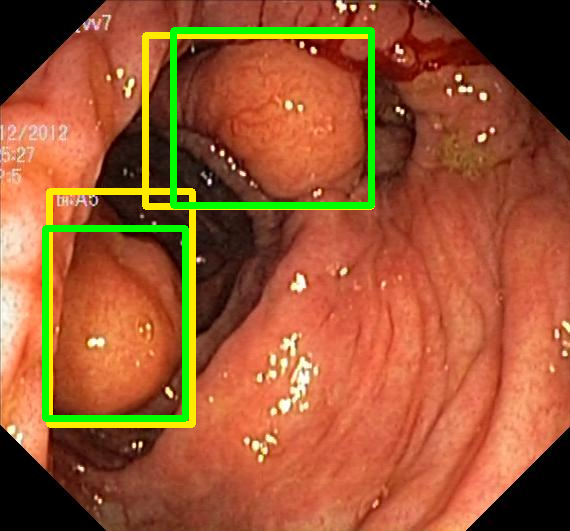

We evaluate the resulting object detection models using the test data, which is pre-processed in the same manner as the validation data, with AP@[.5:.95] (AP for conciseness), AP@.5 (AP5050{}_{50}start_FLOATSUBSCRIPT 50 end_FLOATSUBSCRIPT), and AP@.75 (AP7575{}_{75}start_FLOATSUBSCRIPT 75 end_FLOATSUBSCRIPT) computed for predicted bounded boxes with a confidence score \geq0.05. For all metrics, a higher value indicates better performance. The results are presented in Table VI, and some examples for predicted bounding boxes with a confidence score \geq0.5 are shown in Fig. 1.

RN-HK-MC RN-HK-BT RN-IN-MC RN-IN-BT RN-IN-SL RN-NA-NA Refer to caption Refer to caption Refer to caption Refer to caption Refer to caption Refer to caption Refer to caption Refer to caption Refer to caption Refer to caption Refer to caption Refer to caption VT-HK-MC VT-HK-MA VT-IN-MC VT-IN-MA VT-IN-SL VT-NA-NA Refer to caption Refer to caption Refer to caption Refer to caption Refer to caption Refer to caption Refer to caption Refer to caption Refer to caption Refer to caption Refer to caption Refer to caption

Figure 1: Targets (yellow bounding boxes) and predictions (green bounding boxes) for two randomly selected instances of the Kvasir-SEG test set. For conciseness, we denote ResNet50s with RN, ViT-Bs with VT, Hyperkvasir-unlabelled with HK, ImageNet-1k with IN, MoCo v3 with MC, Barlow Twins with BT, MAE with MA, supervised pretraining with SL, and no pretraining with NA-NA.